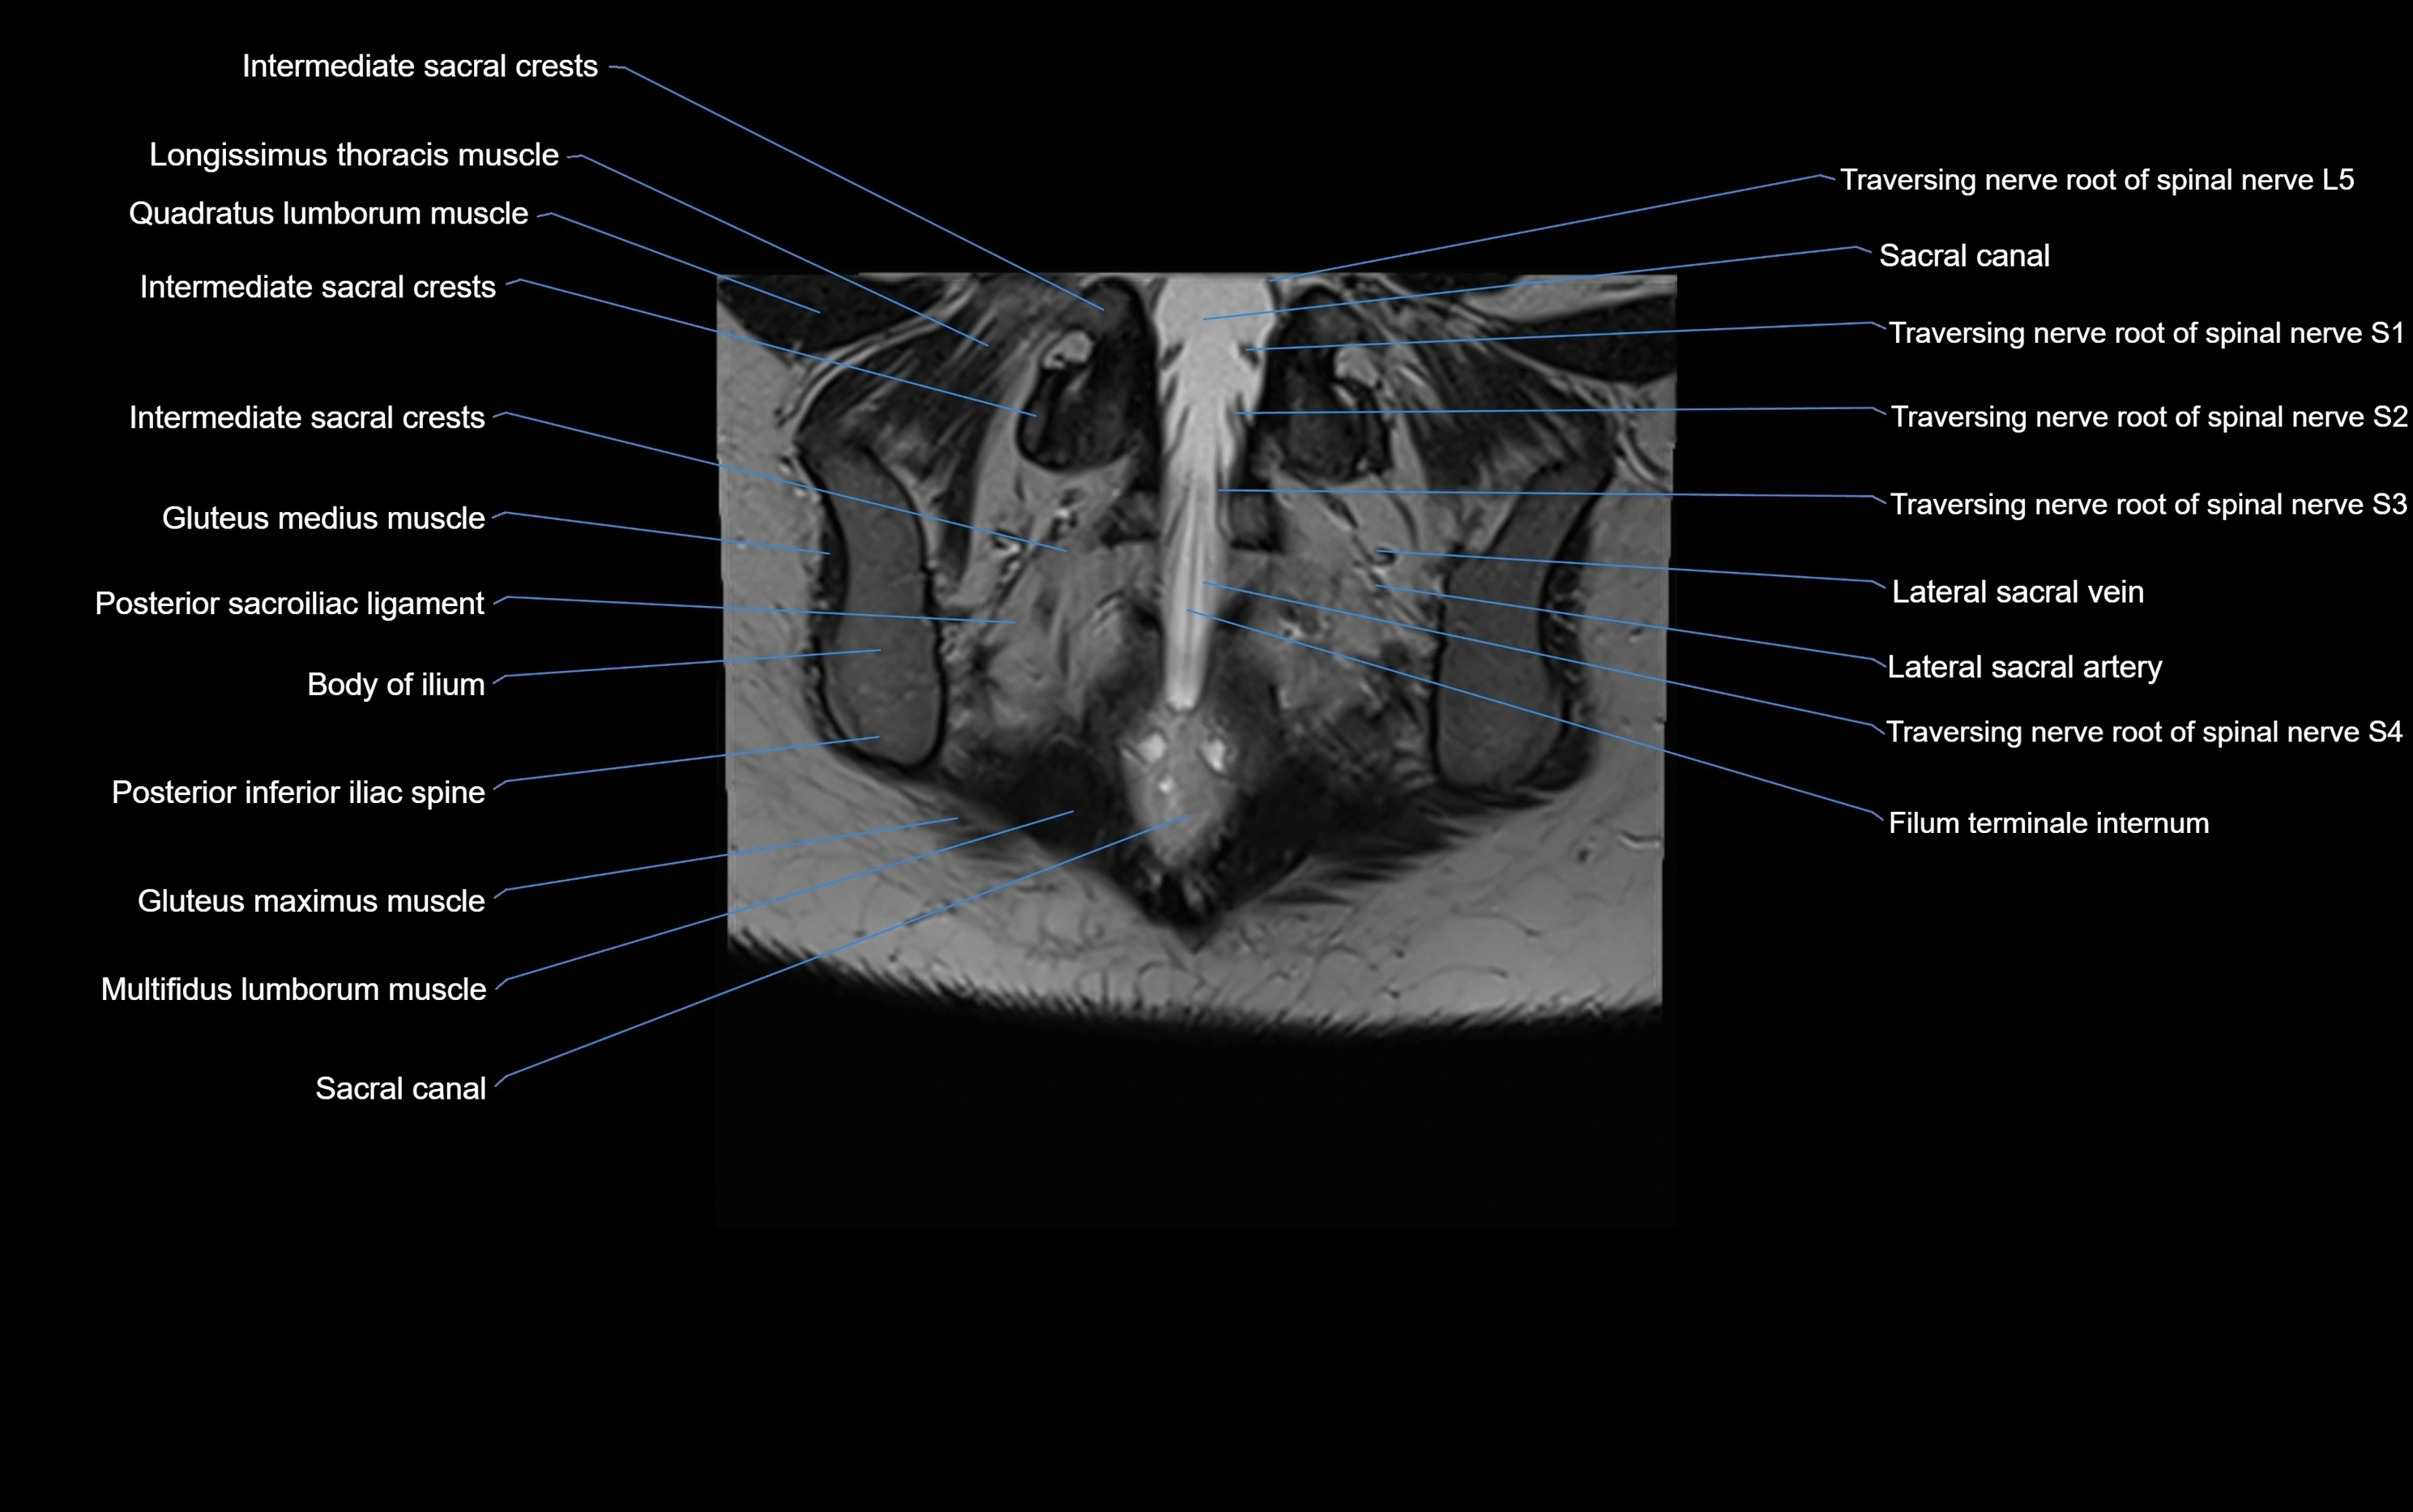

MRI image

image